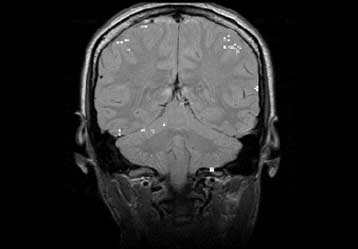

Η πρώτη στον κόσμο έρευνα σε εθνικό επίπεδο που διενεργήθηκε στη Δανία και εξετάζει τη συχνότητα εμφάνισης καρκίνου σε χρήστες κινητών τηλεφώνων υποστηρίζει ότι δεν υπάρχει σχέση των τηλεφώνων αυτών με τους εγκεφαλικούς όγκους, με τους καρκίνους του εγκεφάλου ή των σιελογόνων αδένων ή με τη λευχαιμία. Οι ερευνητές, ωστόσο, δεν αποκλείουν τη σχέση των ραδιοκυμάτων χαμηλής συχνότητας των κινητών με άλλα προβλήματα υγείας, όπως είναι οι ημικρανίες.